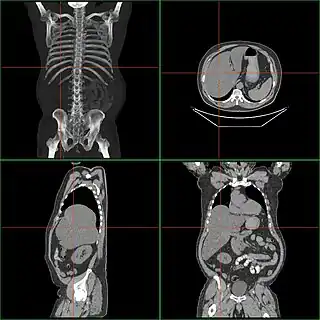

![]() Tomografía computarizada de un caso de hepatomegalia. | ||